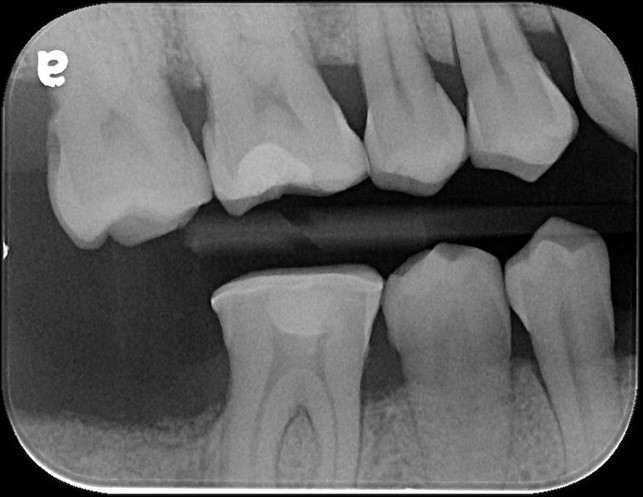

治療前,頰側牙齒斷裂

X光邊緣完整